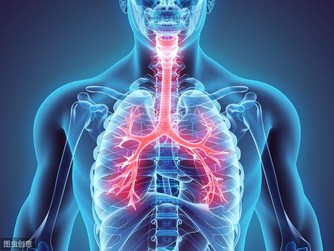

甲減是甲狀腺分泌的甲狀腺激素過少而引發的一種疾病。當甲減發生時,人體新陳代謝減慢,血脂的利用率就會變低,並且在血液中積累、升高,從而引起了高血脂。

而當血脂積累過多就會沉積在血管壁上,並逐步形成動脈粥樣硬化斑塊,造成血管變得狹窄,從而導致心腦血管疾病風險蹭蹭漲~